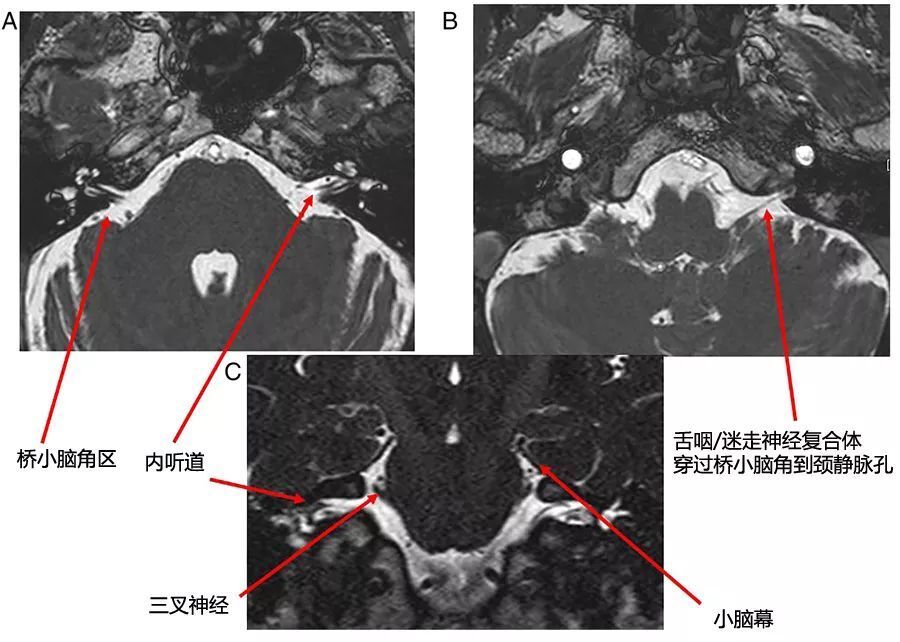

图1  桥小脑角区正常解剖